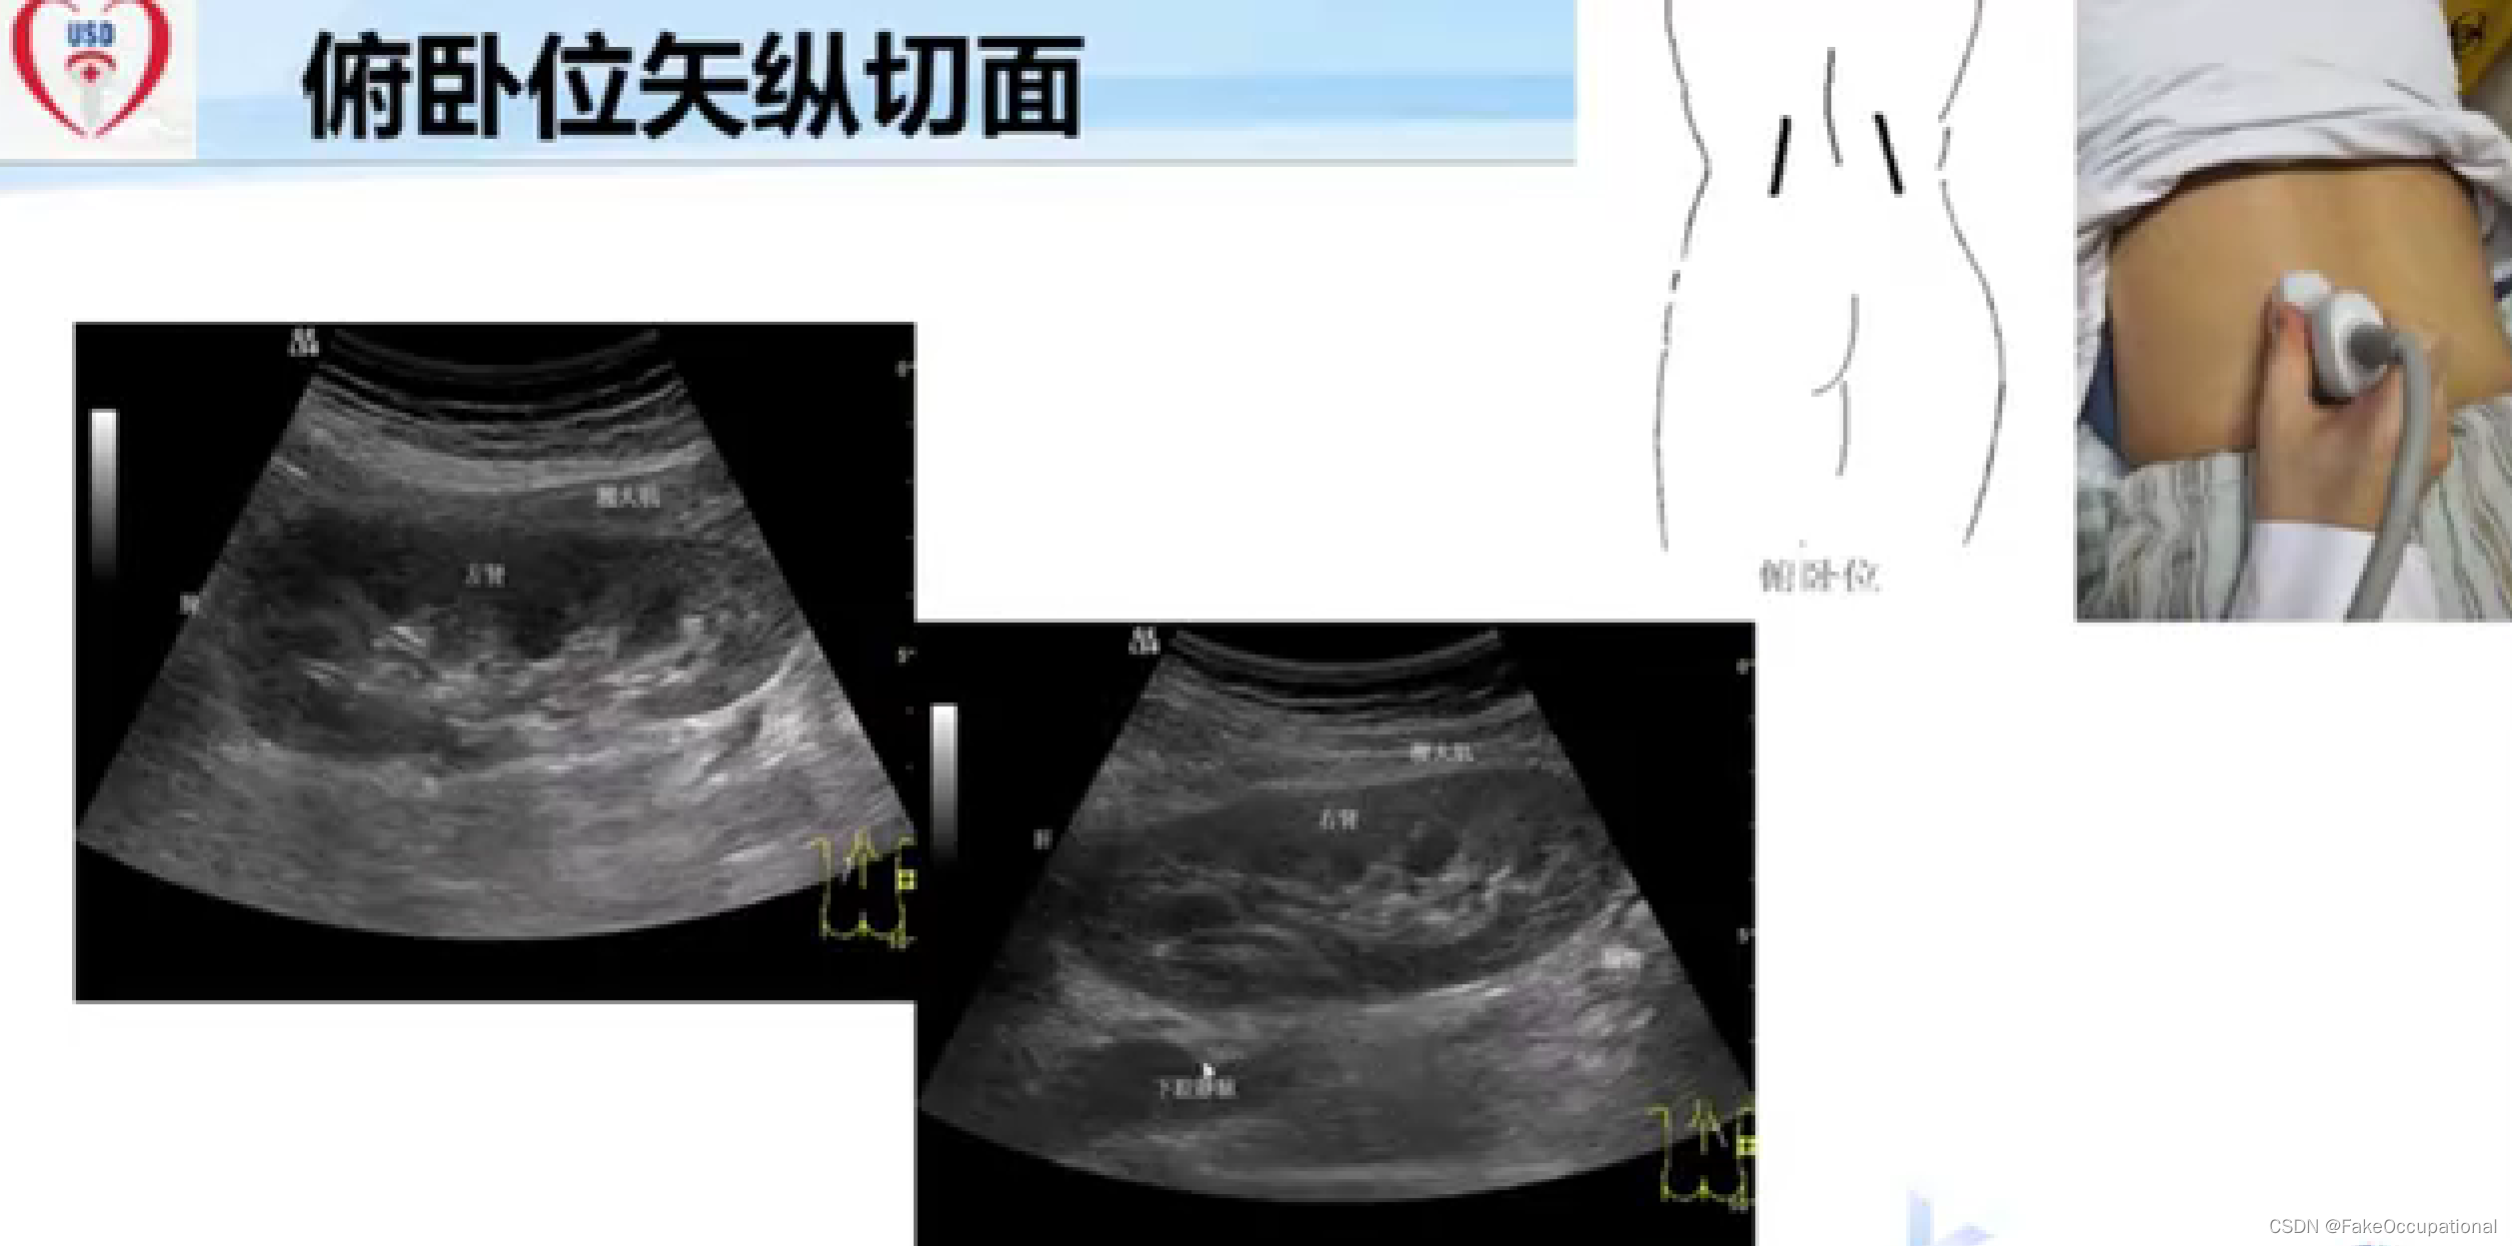

超声检查技术